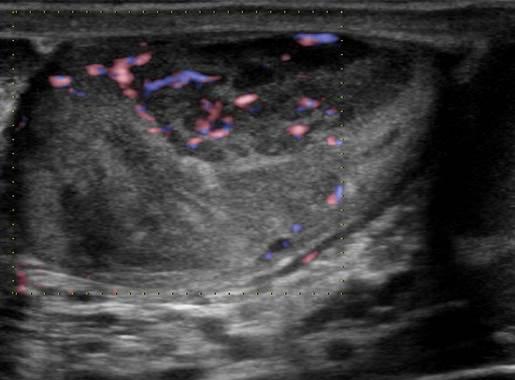

U tinh hoàn

» Thông tin: Nam giới – 35 tuổi.

» Lâm sàng: Sưng tinh hoàn.

# U tinh bào (Seminoma).